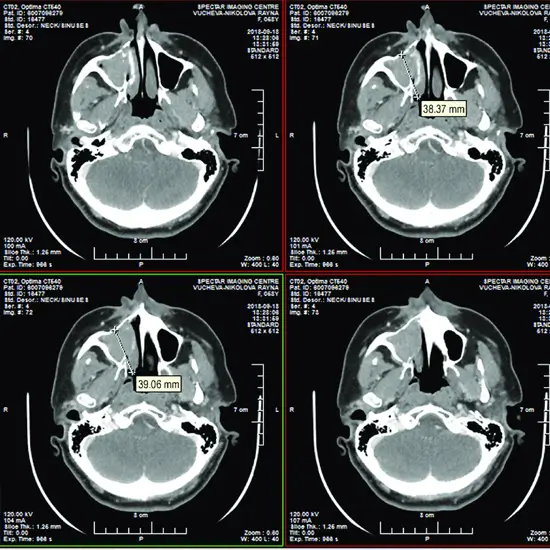

CT (Computed Tomography) Scan Maxilla Axial is an imaging scan that is used to create a detailed and clear image of bones, tissues, skin, and muscles for effective diagnosis of the problem of the upper jaw at the axial plain (left to right). Doctors recommend this scan to detect and identify the infection, injury, and other abnormalities in the maxilla.

Doctors recommend this scan to diagnose the upper jaw and the problem associated with it.

• Infection, Inflammation of the maxillary sinus

• Injury in the upper jaw bone

• Abnormalities, Tumors in maxillary region.

• Advanced periodontal issues

• The disorders of TMJ